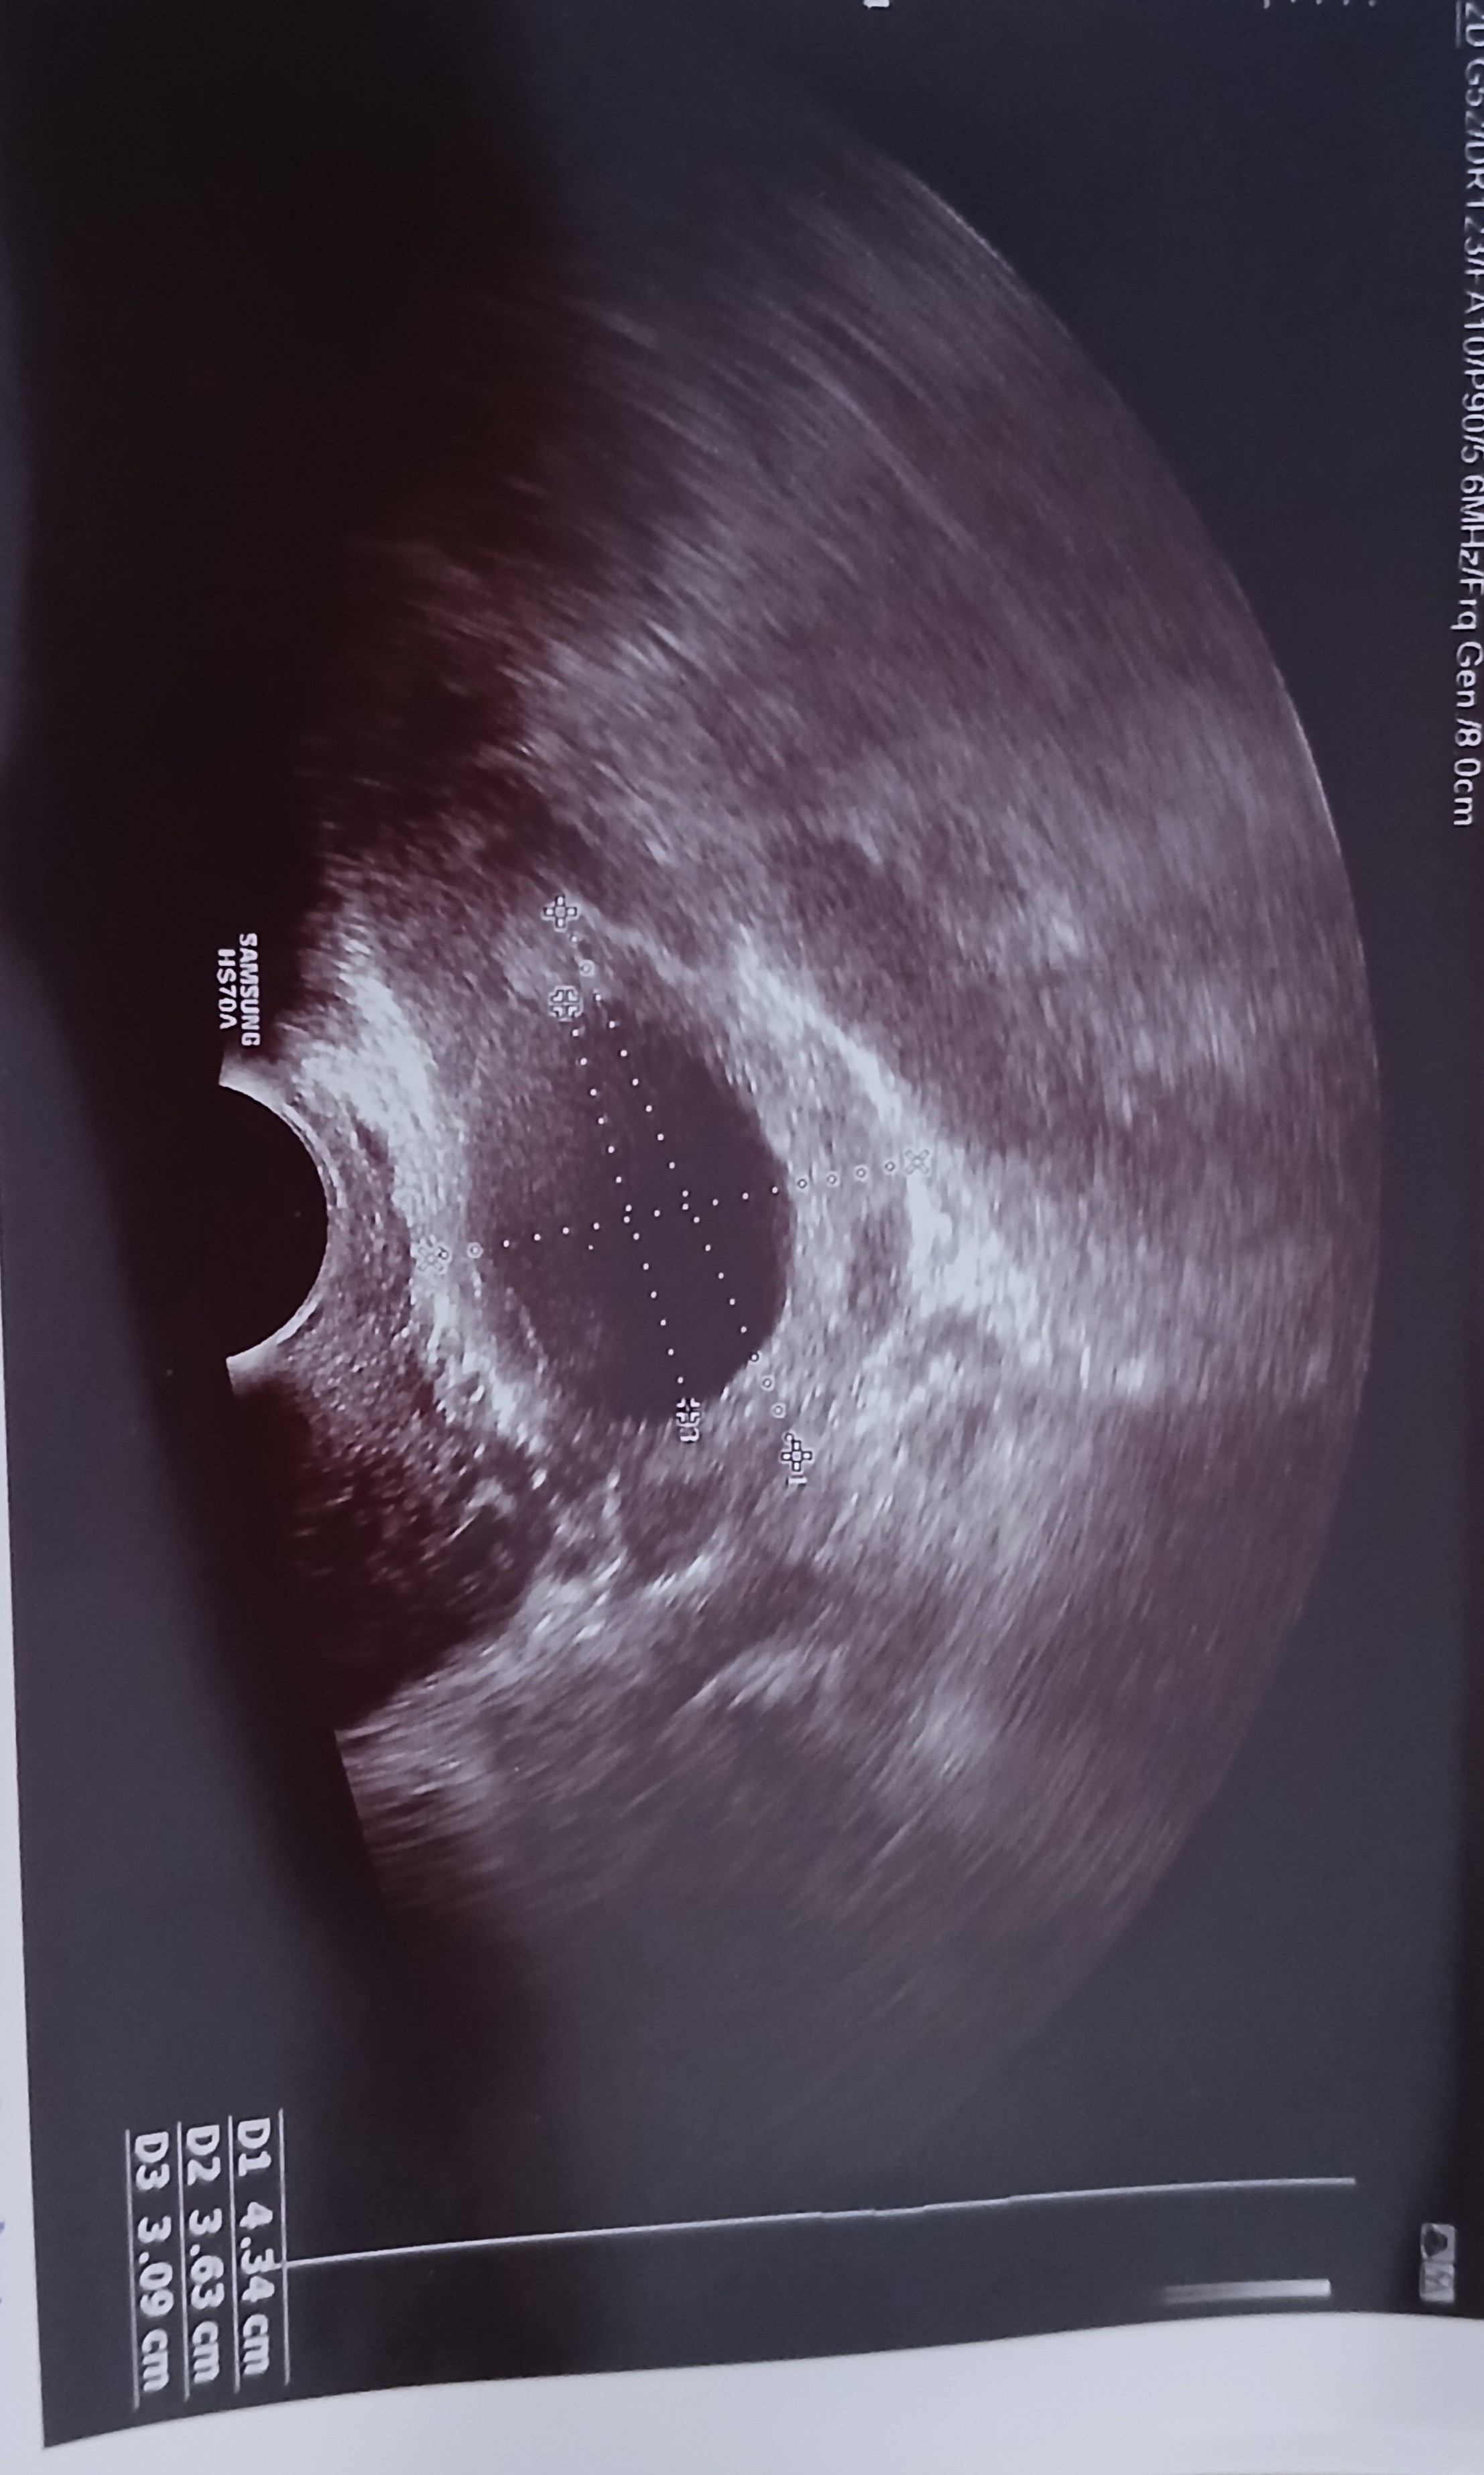

Okres dostałam 16 grudnia, przeszłam ciążę biochemiczną (12 i 13 grudnia pozytywne testy ciążowe, 15 grudnia beta 10) niestety 16.12 zaczęłam krwawić. Dziś 30.12 byłam na monitoringu owulacji lekarz powiedzial że do owulacji nie doszło i najpewniej juz nie dojdzie. Widoczny jest pecherzyk o wielkości 3cm, 2 stycznia mam znów monitoring. Ile mają wasze pecherzyki które pękają? Ponoć do 2,5cm osiągają wielkość nie wiem czy jest jeszcze szansa że pęcherzyk pęknie

Miałam problem z niepekającymi pęcherzykami i nie tylko po wielkości ale i jakoś po budowie lekarz je rozpoznawał już jako torbiel. Fakt faktem że w około 2,2-2,5cm celował z podaniem zastrzyku na pęknięcie 🙂